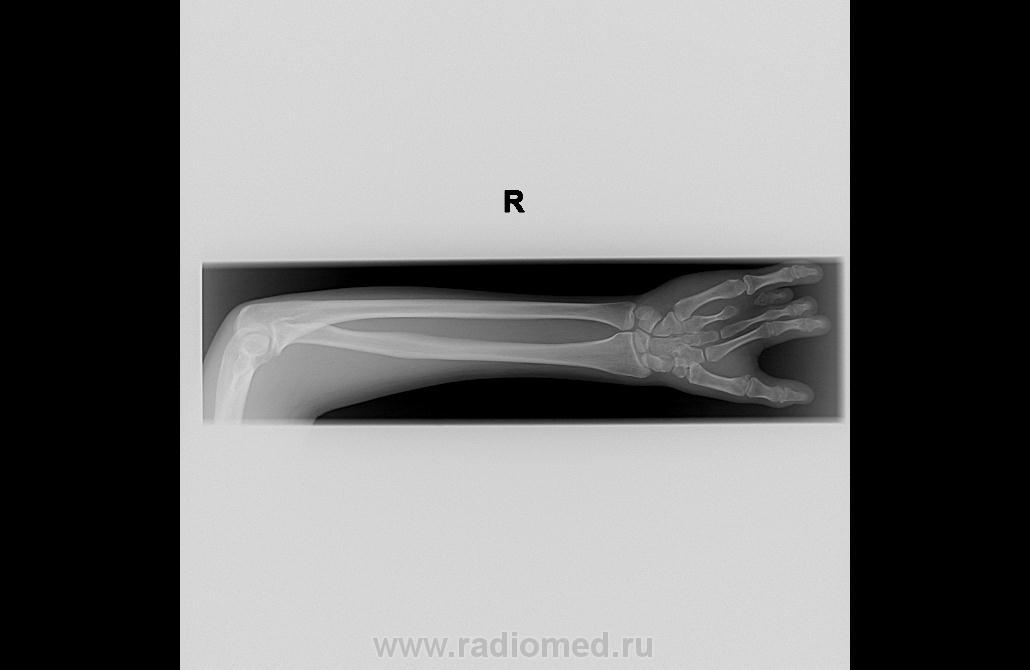

Здравствуйте! Я первый раз поэтому еще никак не могу приспособиться как вставлять изображение. Пациентка 17 лет была на приеме 27.06.2012 г. Ваше мнение.

Здравствуйте! Нет обратились впервые. Немного странно почему в таком возрасте обратились. Мое мнение здесь брахифалангия, брахидактилия IV пальца. А вот III палец обратите внимание на среднюю фалангу. Жду вашего мнения.

Какой сложный порок, только 1 палец нормален. Отсутствуют средние фаланги, кажется... Мизинец огромный, но думаю, что функциональность не сильно страдает. Как назвать - затрудняюсь сказать, ни разу с подобными пороками не встречалась... Наверное, Ola-la сможет помочь.

А вы уверены, что это фаланга? По-моему тамв 2, 3, и 5 пальцах отсутствует средняя фаланга. В 3 пальце пястная кость раздвоена и сращена с оновной фалангой. В 4 пальце гипоплазия пястной кости и только ногтевая фаланга. И ещё пожелание, сделайте нормальную кисть в прямой проекции. Заодно и противоположную.

Кстати, а остальные кости развиты нормально? Поражение только в этой кисти? И как выглядят стопы? Существуют множественные поражения верхних конечностей в связи с недоразвитием по длине, количеству, бывают как одно-, так и двухсторонние. Что в данном случае?

По-моему, явная аномалия развития-сращение, недоразвитие. Вопрос: пациентка с жалобами пришла? Или оформляют инвалидность?